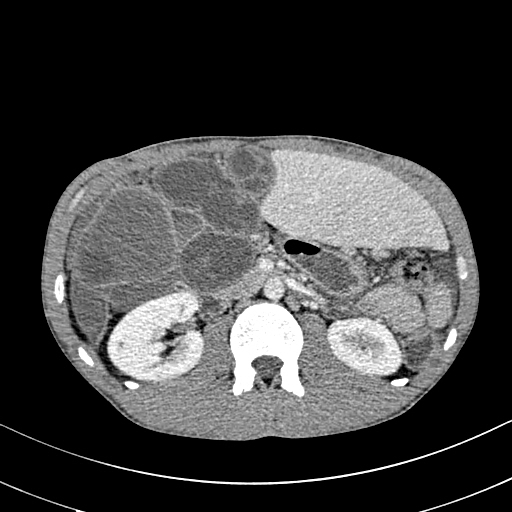

Histology is similar to hamartomas, although some state a lymphangiectasic or neoplastic nature, without any malignant potentiality [3]. Ultrasonography documents mono-or multiloculate fluid-superfluid lesions with a substantial lack of flow with Doppler mode (figure/patient 1-2). Computer Tomography (CT) describes low attenuation masses with occasional fluid level and minimum septal and peripheral enhancement. Magnetic resonance imaging (MRI) detects iso-or hyposignal on T1-weighted sequences and hyper-signal on T2-weighted sequences, a halo of enhancement around the septa of macro-cystic lesions and peri lesional lymphoedema (figure/patient 2-3) [4].

Sclerotherapy is nowadays largely employed in case of macro-cystic or mixed lymphangiomas, where the size of the cysts allows them to be punctured and a wider distribution of the agent is achieved. However, OK-432, bleomycin and above all doxycycline have recently proved effective also with micro-cystic variety [2]. The rationale comes from the observation that lymphangiomas can reduce their size or regress after a spontaneous infection, probably due to the destruction of the epithelium, reduction of lymph production and collapse of the cyst: thus, the idea of adopting sclerosing agents to mimic such an effect. Puncture of the dominant cyst (or more, in case they are noncommunicating) with a fine needle (20 G or more) is followed by aspiration (in order to enhance the SA effect) and injection, in one or more times, of the sclerosing agent, using the same amount as the aspirated fluid (if impossible, half of the lesion's volume). It can be repeated in case of partial response or whenever more administrations are chosen, each session being separated by weeks up to a month. General or loco-regional anaesthesia is preferred in children or uncooperative patients and in adults or small cystic malformations, respectively; the patient's position is changed many times to favour a uniform distribution of the agent and the treatment lasts up to two hours. A postoperative compressive bandage is advised in order to increment the time of contact between the solution and the cyst's wall and to prevent seroma formation, bleeding or effusion of the SA. The procedure can be performed under ultrasound or CT: the first is cheaper, more available, does not employ ionising radiations (thus being advisable in children and young adults), defines better the different components within the lesion, grants different cranio-caudal angles and reduces the risk of accidental puncture of large blood vessels; however, it is operator-dependent and offers a narrow field of view, with the risk of missing some important findings, especially at the post-procedure check. CT instead is easier to perform and provides a more panoramic view but implies radiation and the needle path to lie on the axial plane with its full length [1]; a detailed example of this procedure is offered in figure (patient) 4, whereas figures (patients) 5 and 6 show examples of successful outcomes comparing lymphangiomas before and after sclerotherapy. Fluoroscopic guidance is also reported, especially in case of the most superficial lesions, with the possibility to inject contrast medium into the lesion in order to highlight communications between the intra-lesional spaces and establish the amount of SA to be used [4]. Complications include intraoperative bleeding (due to their dysplastic nature), accidental injuries to nerves, vessels, organs and other tissues (due to extravasation), peri-lesional fibrosis and aesthetic sequelae (due to necrosis followed by second-intention reparation), dosedependent cardio-pulmonary toxicity (especially with bleomycin) and acute respiratory insufficiency (with large lymphangiomas undergoing inflammation, necrosis and quick volumetric expansion); the latter could be managed with dexamethasone or, preferably, avoided by splitting the treatment in more sessions [7]. An example of follow-up program would consist of a clinical examination after one to three weeks, ultrasonography after six to twelve weeks and then (depending on the results of ultrasound) MRI, unless evidence of early recurrence or any other complication occurs [8]. A review by Adams et al didn't prove the superiority of sclerotherapy over surgery but showed it was the treatment of choice in most major paediatric vascular anomaly centres: surgery was reserved for refractory cases, with sclerosing agents not improving either clinics or aesthetics, micro cystic lesions or those associated with life-threatening airway obstruction. Nowadays there are no worldwide-accepted guidelines and patient selection seems to guide the choice. In addition, neither surgery nor sclerotherapy can guarantee complete healing with just one session: it is actually advisable to perform multiple treatments or combine them [1].